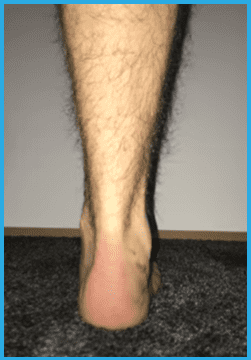

Left/Top: Illustration of flat feet before surgery.

The left/upper image shows auntreated flat feet before surgery. The right/bottom picture shows flat feet treated with Shark Screw® after surgery.